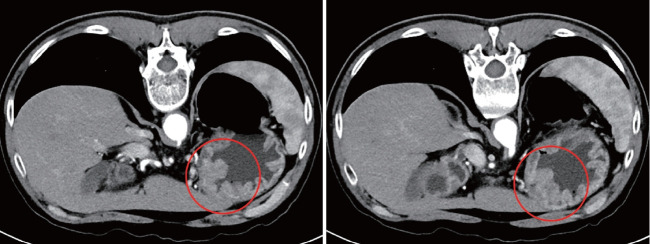

胃腺癌伴肠母细胞分化(GAED)是罕见的,其临床病理特征没有很好的文献记载。然而,报告表明它表现出比传统胃腺癌更具侵袭性的特征,包括淋巴结转移或肝转移。在此,我们报告一例GAED的快速复发和疾病进展。一名55岁男性,被诊断为胃癌(GC),最初的内镜检查结果提示胃癌晚期。由于没有淋巴结或远处转移的证据,他接受了根治性切除。本病为早期胃癌,局限于粘膜下层,最终病理结果无淋巴结转移的证据。然而,手术后6个月,腹部计算机断层扫描发现多发肝转移;病理结果与胃癌转移一致。原发癌病理标本的免疫组化结果显示甲胎蛋白和sal样蛋白4阳性,提示肠母细胞分化,这被认为与快速复发和疾病进展有关。

Gastric adenocarcinoma with enteroblastic differentiation (GAED) is rare and its clinicopathological characteristics are not well documented. However, reports indicate that it exhibits more aggressive characteristics, including lymph node metastasis or liver metastasis, than a conventional gastric adenocarcinoma. Herein, we report a case of GAED with rapid recurrence and disease progression. A 55-year-old male, diagnosed with gastric cancer (GC), demonstrated initial endoscopic findings suggestive of advanced GC. He underwent curative resection since there was no evidence of lymph node or distant metastases. The disease was reported as an early GC that was confined to the submucosal layer, without evidence of lymph node metastasis in the final pathological results. However, six months after surgery, multiple hepatic metastases were found during abdominal computed tomography; the pathological results were consistent with metastasis from the GC. Immunohistochemistry of the primary carcinoma pathological specimens showed positive results for alpha-fetoprotein and sal-like protein 4, suggesting enteroblastic differentiation, which is thought to be associated with rapid recurrence and disease progression.